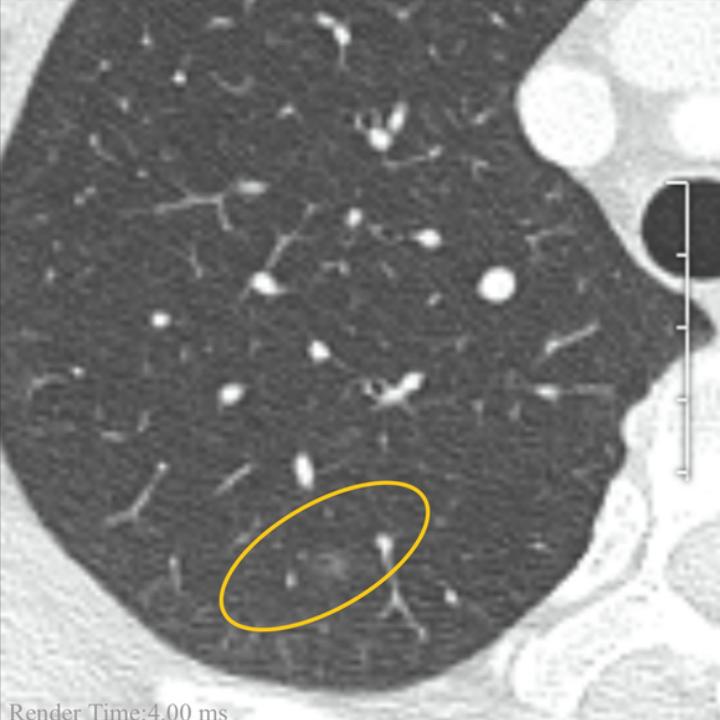

截止今年5月暂时结疗,才关注起磨玻璃结节,从pect ct 去年的6mm,到半年后到今天薄层扫描为5mm,今天去了上海复旦肿瘤看了,医生说就是原位癌,方法就是手术与观察由自己决定,爱人听到这个消息五雷轰顶,当时表示不治了………

2013年5月增强CT检查,上海复旦肿瘤医院

报告日期:2023/5/2216:33:00

检查方法:两肺纹理清晰,走向自然,右肺上叶后段见

一约5mm磨玻璃密度结节影,所见各支气管腔通畅,两肺门及纵隔未见肿大淋巴结,胸膜无增厚,胸腔内无积液。

放射学诊断:右肺上叶后段GGO,建议随访。